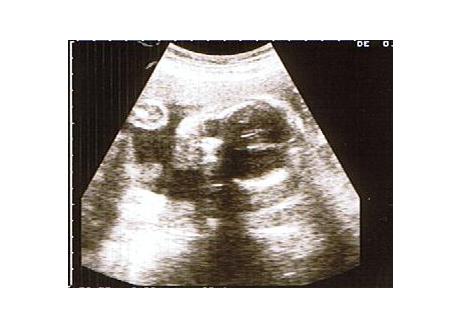

おなかの中の幸平 |ω・)